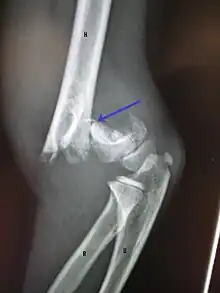

| An elbow X-ray showing a displaced supracondylar fracture in a young child | |

A supracondylar humerus fracture is a fracture of the distal humerus just above the elbow joint. The fracture is usually transverse or oblique and above the medial and lateral condyles and epicondyles. This fracture pattern is relatively rare in adults, but is the most common type of elbow fracture in children.[1] In children, many of these fractures are non-displaced and can be treated with casting. Some are angulated or displaced and are best treated with surgery. In children, most of these fractures can be treated effectively with expectation for full recovery.[2] Some of these injuries can be complicated by poor healing or by associated blood vessel or nerve injuries with serious complications.